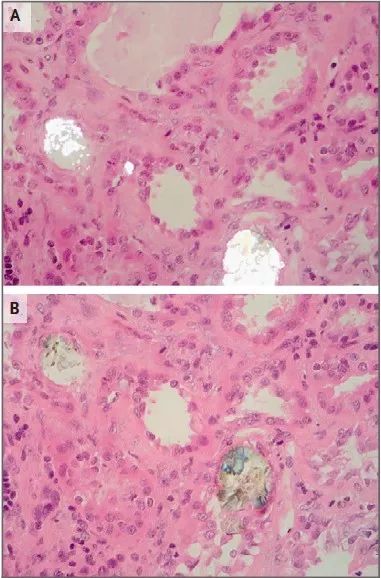

肾活检发现草酸钙结晶,提示草酸盐肾病(肾小管腔内草酸盐结晶沉积引起的肾脏损害)是该患者肾功能突然下降的最可能原因,矛头指向了奥利司他。因为这种药物带来的脂肪吸收不良会导致肠内脂肪酸增加,而这些脂肪酸与钙的竞争性结合可能导致肠内草酸盐吸收增加、草酸盐经肾脏排泄增加(继发性高草酸尿)以及肾小管草酸钙沉积的趋势。

注: A偏振光显微镜结果,B苏木素伊红染色结果

图1 肾活检提示草酸钙结晶